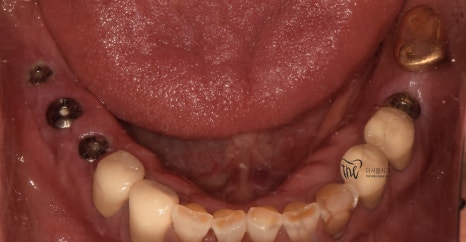

우선 교합면에서 바라보게 되면,

곳곳에 치아 결손 부위가 관찰이 되는데

이가 빠진지 시간이 꽤나 오래 되셨다는 것을

한 눈에 알아차릴 수 있습니다.

바로 결손부위를 보게 되면, 골 폭이 상당히

좁아져 있는 것을 볼 수 있는데 이는 치아 상실 후

방치 된 시간이 꽤나 오래 되었다는 것에 따른

반증이기 때문입니다.